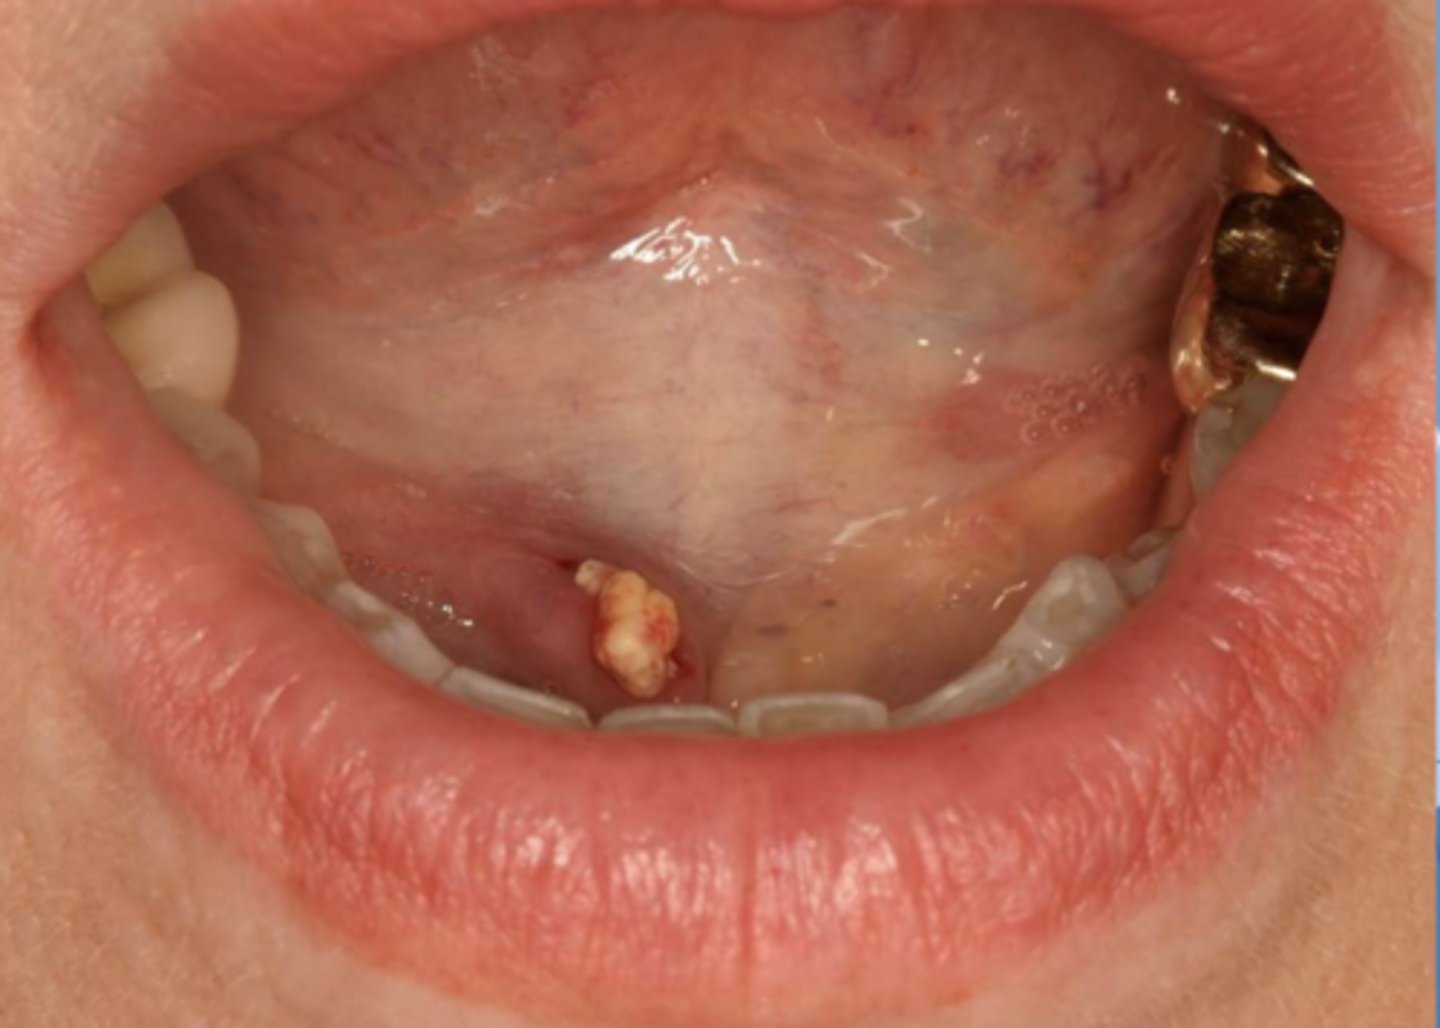

Sialolitiasis

Calcified structures within the salivary duct system lead to ________

Sialolithiasis

Patient present to your office complaining of pain upon salivation. A small firm, non-fluctuant mass is visible on the floor of the mouth lateral to the midline. Radiograph shows a radiopaque mass in the location of interest. What is the diagnosis?

ID the pathology:

Swelling in wharton's duct

ID the pathology during surgery:

Associated with pain upon salivation

What pathology is associated with pain upon salivation?

submandibular gland

80% of Sialolithiasis are associated with what gland?

Radiopaque mass

What is the radiographic features of a

Sialolithiasis?

ID the pathology based on the histology findings:

- Laminated calcified structure with central nidus

- Milking stone toward duct orifice